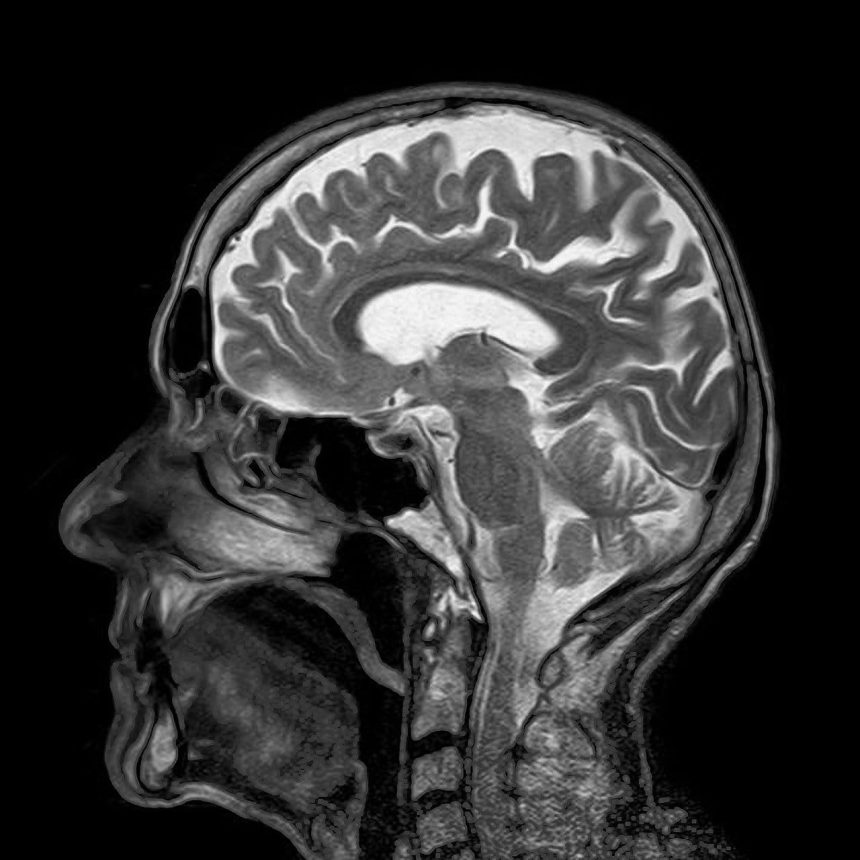

Geçtiğimiz on yıl boyunca bazı yapay zekâ modelleri, belirli hastalıkların veya nöropsikiyatrik durumların erken teşhisi ve incelenmesi konusunda umut verici sonuçlar ortaya koymuştur. Örneğin, manyetik rezonans görüntüleme adı verilen ve vücuda müdahale gerektirmeyen (noninvaziv) bir teknikle toplanan çok sayıdaki beyin taramasını analiz eden yapay zekâ; tümörler, felçler ve nörodejeneratif hastalıklarla ilişkili kalıpları açığa çıkarabilmektedir. Bu yetenek, söz konusu rahatsızlıkların çok daha erken safhalarda teşhis edilmesine yardımcı olabilir.

Kann ve meslektaşları tarafından geliştirilen genel model BrainIAC, MRI kullanılarak toplanan toplam 48.965 beyin görüntüleme taraması üzerinde önceden eğitilmiştir. Model, çoğunlukla etiketlenmemiş verilerden kalıpları öğrenmeyi sağlayan, kendi kendine denetimli öğrenme olarak bilinen bir yaklaşımla eğitilmiştir. Bu kapsamlı eğitim sayesinde model, insan beyninin yapısı ve organizasyonunu oluşturan kalıplar hakkında derinlemesine bilgi edindi. İlk ön eğitim aşamasının ardından model; bir hastanın MR taramalarından yola çıkarak belirli hastalıkların ve nöropsikiyatrik durumların tespit edilmesi veya ilerleyişinin incelenmesi için kolayca uyarlanabilir hale geldi.